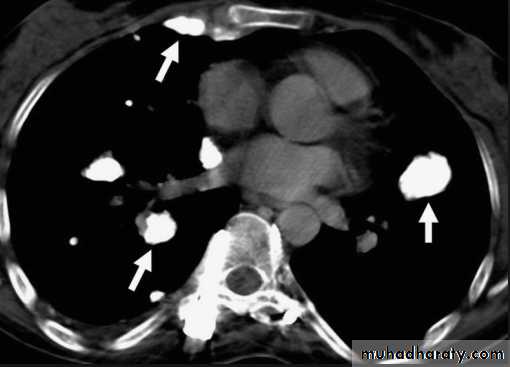

Differential diagnosis of multiple spherical lesions:

1 - Metastasis.

2-Hydatid cyst.

3- Sarcoidosis.

4- Rheumatoid nodules.

5 – pneumoconiosis

6- Histoplasmosis